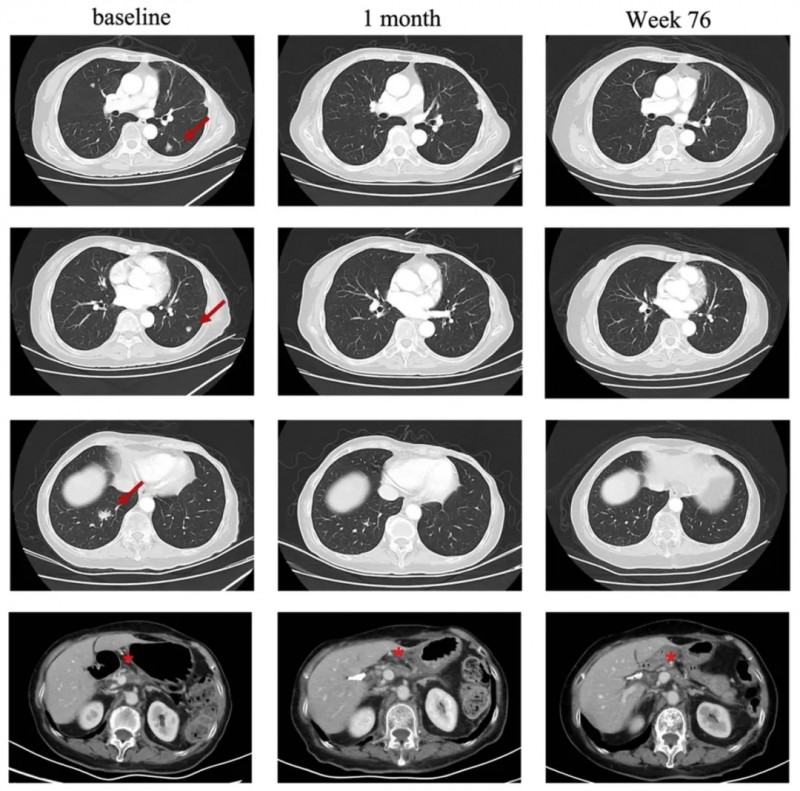

一项应用CT041(针对CLDN18.2阳性实体瘤的自体CAR-T候选产品)治疗胰腺癌的临床研究,曾报道过一个振奋案例。该患者是一位75岁pT2N0期胰腺癌患者,既往接受手术联合S-1单药化疗后疗效不佳,出现肺部肿瘤进展,基于其CLDN18.2表达水平为3+/60%,遂成功入组临床试验。

结果显示:CT041治疗第4周,患者达到部分缓解(PR);后续肺转移靶病灶完全消失,进一步达到完全缓解(CR),截至2023年7月最后一次随访,肿瘤控制情况持续良好。

▼该患者在CT041治疗前后,肺部病变的放射学评估

▲图源“BMC”,版权归原作者所有,如无意中侵犯了知识产权,请联系我们删除